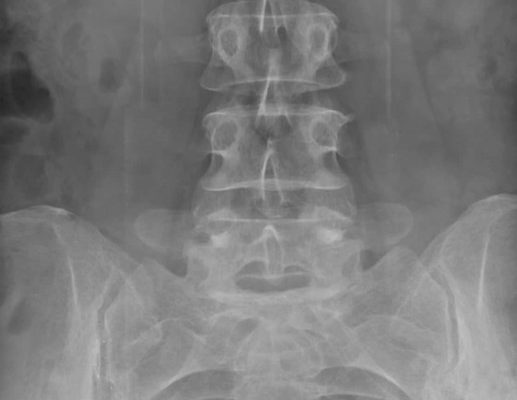

При прямом обследовании пациента горизонтально кладут на кушетку, и излучающая часть рентгеновского аппарата проходит над ним. Диагностика проводится в нескольких проекциях — это позволяет поставить точный диагноз и заметить даже те отклонения, которые скрыты в прямой проекции.

В некоторых случаях врачи осматривают не только копчик, но и прилегающие к нему отделы. Это позволит поставить точный диагноз, выявить дополнительные патологии или осложнения. После рентгена копчика результаты можно будет получить в тот же день в течение нескольких часов или на следующий день.

Что покажет рентгеновский снимок

Рентгенологическое исследование помогает визуализировать аномалии, которые невозможно увидеть невооруженным глазом. О травмах копчика можно только догадываться, но окончательный диагноз можно поставить только на основании множественных проекционных рентгенограмм. Показ данных скрининга

- вывих элементов в крестцовой области;

- трещины;

- остеохондроз;

- кисты;

- растяжение связок;

- ушиб;

- воспалительные процессы;

- метастазирование опухоли;

- остеомиелит;

- деформации;

- вспышки остеопороза.

В большинстве случаев врачи ставят диагноз на основании результатов рентгенологического исследования. Например, перелом копчика хорошо виден и не оставляет сомнений. Если врач не удовлетворен результатами обследования, поскольку предполагаемая патология не была выявлена на рентгеновском снимке, он порекомендует альтернативные методы диагностики.